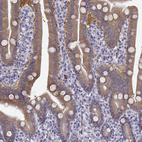

Immunohistochemistry analysis in human duodenum and tonsil tissues using HPA040671 antibody. Corresponding CREB3L3 RNA-seq data are presented for the same tissues.